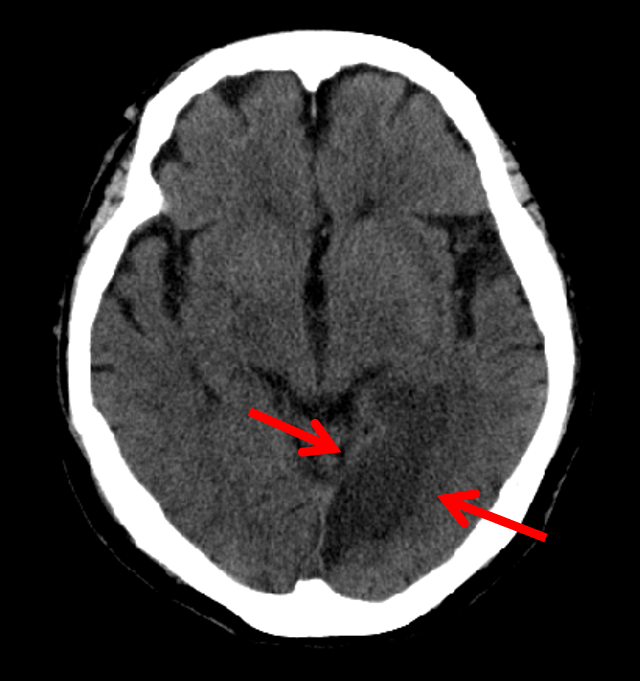

Figure 11: BCT most likely to have an abnormality according to the logarithm posterior probability out of the 33 abnormal BCTs used for testing (subdural hematoma along the left cerebellar tentorium).

Refer to caption

Figure 12: BCT most likely to have an abnormality according to the logarithm posterior probability out of the 33 abnormal BCTs used for testing. This is an enlarged version of a part of Fig. 11, and the lesion is pointed out with red arrows.

Figure 13: BCT second most likely to have an abnormality according to the logarithm posterior probability out of the 33 abnormal BCTs used for testing (acute infarction in the left posterior cerebral artery territory).

Figure 14: BCT second most likely to have an abnormality according to the logarithm posterior probability out of the 33 abnormal BCTs used for testing. This is an enlarged version of a part of Fig. 13, and the lesion is pointed out with red arrows.

Figures 11 and 12 show the BCT most likely to have an abnormality according to the logarithm posterior probability out of the 33 abnormal BCTs used for testing. Figures 13 and 14 show the BCT second most likely to have an abnormality according to the logarithm posterior probability out of the 33 abnormal BCTs used for testing.